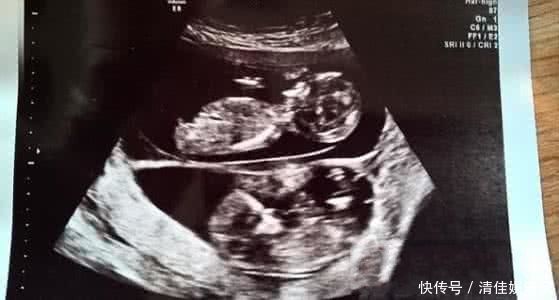

在美国阿肯色州,一名孕妇在怀孕五个月后例行超声波检查时令医生大吃一惊,因为医生们发现该名孕妇在腹中的女婴旁边,再怀有一名胎龄更小的男婴。

据社交媒体报道,阿肯色州KFSM-TV电视台接获的声明指出,相信格罗文伯格太太是在怀有女婴吉莉恩整整五个月后才怀有男婴赫德森的。 妇产科医生迈克尔说:“这种情况很少见,但存在这种可能性。我们得等婴儿出生,给他们做染色体等检测后才能确定。”